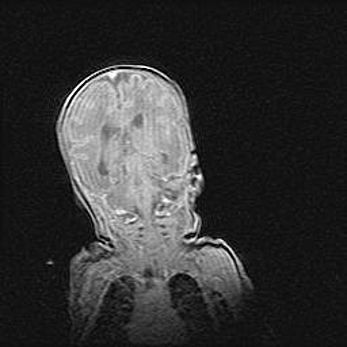

Аномалия Денди-Уокера. Признаки гипоплазии мозолистого тела.

Возраст: 5 месяцев 3 дня

Вес: 5550 г

Пол: мужской

Окружность головы: 39 см

Срок гестации: 40 недель

Аномалия Денди-Уокера – это порок развития головного мозга, для которого характерна триада симптомов: гипотрофия или аплазия червя мозжечка и/или полушарий мозжечка, расширение четвёртого желудочка с формированием ликворной кисты задней черепной ямки, гипертензионная гидроцефалия различной степени.

Гипоплазия мозолистого тела относится к дефектам внутриутробного этапа развития мозговой ткани, возникающим в процессе закладки структур головного мозга, что происходит на начальных этапах развития эмбриона.